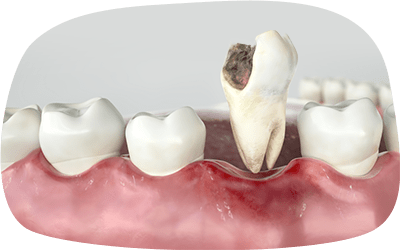

根管治療とは、歯の内部にある神経や血管が通る部分(根管)を治療する方法です。虫歯が進行して神経まで達した場合や、感染による炎症が起きた場合に行われます。

虫歯を放置すると

どうなる?

感染が顎骨に広がり、骨が溶け最悪の場合、抜歯が必要になる場合があります。

全身に悪影響を及ぼす可能性があるため、早めの治療が必要です。